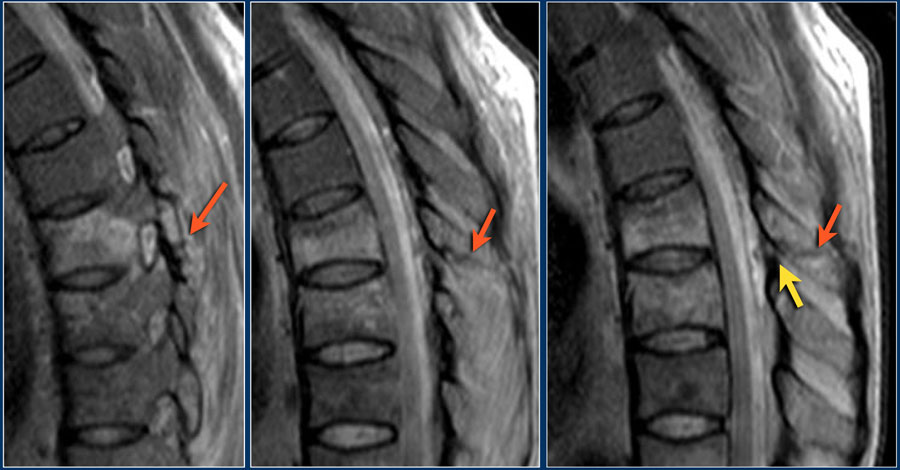

Các hình ảnh là của một bệnh nhân với hình ảnh cột sống tre điển hình do viêm cột sống dính khớp.

Sau khi ngã ngửa, không thấy gãy xương trên phim X-quang.

Tuy nhiên, CT cho thấy một đường gãy mảnh qua mặt trước thân đốt sống và cả qua mỏm gai.

Tiếp tục xem các hình ảnh MRI.